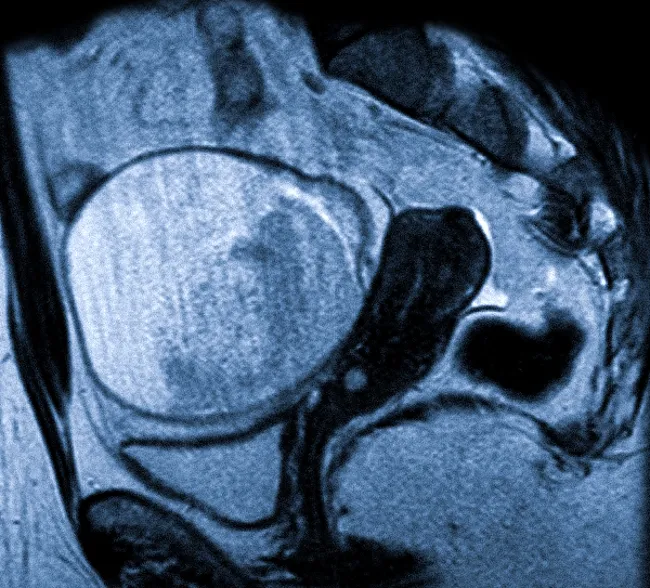

На изображении отображена дермоидная киста (тератома) яичника на МРТ-снимке.

Стол с пациенткой помещается внутрь томографа после установки градиентных катушек в нужной зоне. Генераторы, расположенные в отверстии, создают равномерное магнитное поле, необходимое для резонанса заряженных частиц. Чувствительные детекторы фиксируют ответ и передают его для анализа. Сложные алгоритмы обрабатывают информацию, создавая послойные изображения, которые отражают состояние матки, яичников и расположенных рядом анатомических структур.

Сканирование проходит в аксиальной, сагиттальной и коронарной проекциях. Если требуется, создается трехмерная модель исследуемой области, помогающая уточнить местоположение патологического процесса и взаимодействие пораженных тканей с нормальными.